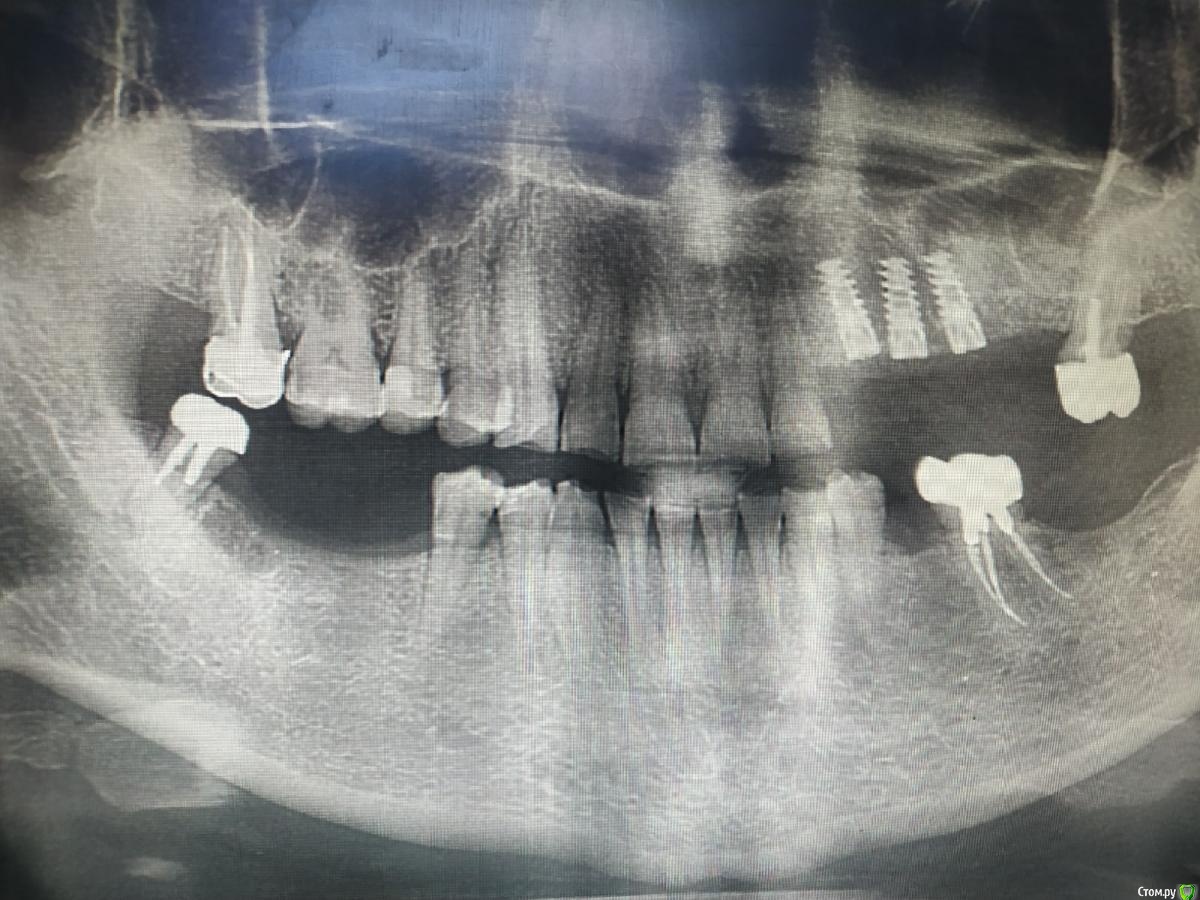

kuziy12 Опубликовано 2 ноября, 2020 Поделиться Опубликовано 2 ноября, 2020 Имплантация с синус лифтингом. Беда с позицией 2.3. Коронки на cad\cam, наносил розовую керамику и красил все сам. Сваливать не на кого) До: После имплантации: Формики: Десна: Постоянная конструкция: Улыбка: 3 Ссылка на комментарий

kuziy12 Опубликовано 9 октября, 2021 Автор Поделиться Опубликовано 9 октября, 2021 Дабы не плодить темы, выложу тут. Докрутил пациента полностью)) Ортопедия тоже моя. От переустановки импланта в области клыка отказалась. Ссылка на комментарий